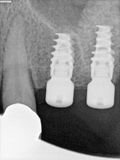

fredlibc | all galleries >> Galleries >> MWang - ulq - CAS-lift and implant placement > R9.jpg